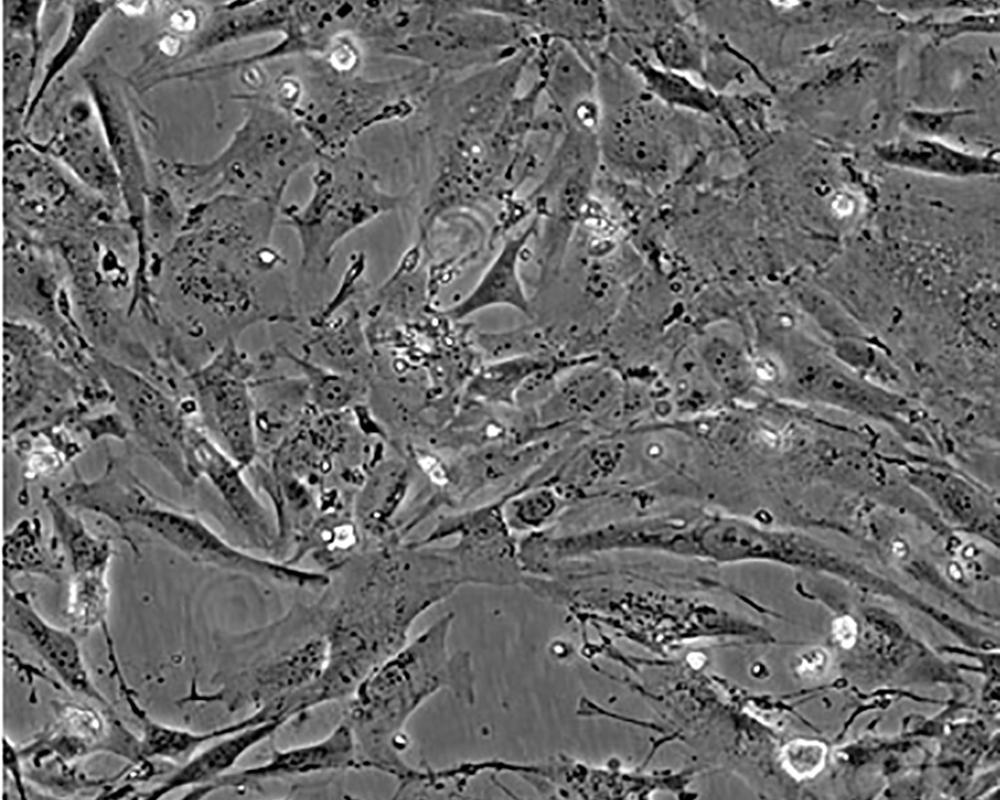

細胞描述 The Hs 578T line had a mixed polygonal morphology initially, but a stellate cell type was selected for during passage and by cloning. Aggregates of casein protein granules, desmosomes, tight junctions, lipid droplets and vesicularized smooth endoplasmic reticulum were observed by electron microscopy. As with Hs 578Bst, no estrogen receptors or endogenous viruses were detected.